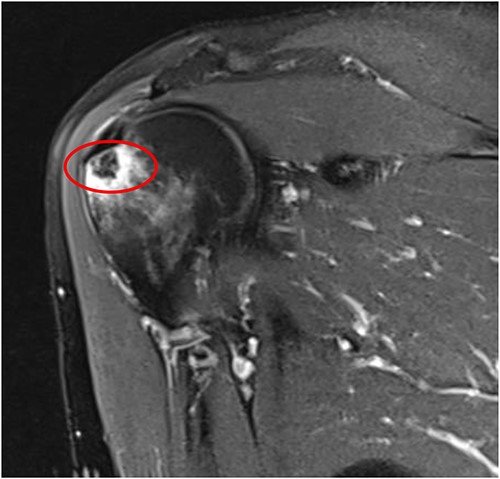

An MRI of the right shoulder showed calcifications over the supraspinatus tendon with an intraosseous lesion mimicking an aggressive or benign skeletal neoplasm (see Figs 2 and 3).

Coronal T2 image of right shoulder showing hypointense lesion; note: the red circle indicates the intraosseous extension of calcified deposits originating from calcified supraspinatus tendon, with surrounding marrow edema.

Axial T2 image of right shoulder showing hypointense lesion; note: the red circle indicates the intraosseous extension of calcified deposits originating from calcified supraspinatus tendon, with surrounding marrow edema.